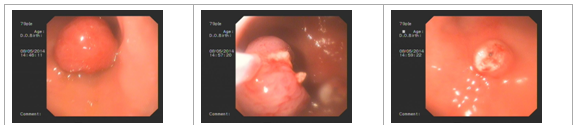

張**,男,74歲,因腹痛半年余來(lái)我院消化內(nèi)科門(mén)診就診,入院后行電子結(jié)腸鏡檢查,直腸可見(jiàn)息肉3個(gè),直徑0.7×0.6-0.8×0.9CM,帶蒂,表面充血水腫,經(jīng)腸道準(zhǔn)備后在內(nèi)鏡下行息肉電凝術(shù)及電切術(shù),手術(shù)順利,術(shù)中見(jiàn)少量出血,給予內(nèi)鏡下止血治療,術(shù)后安全返回病房,恢復(fù)良好。

高**,男,53歲,因腹痛10余天入院,入院后行電子胃鏡檢查,顯示胃體大彎側(cè)可見(jiàn)一2×2cm的息肉,表面光滑,在內(nèi)鏡下行息肉電凝術(shù)及電切術(shù),手術(shù)順利,術(shù)中無(wú)明顯出血,術(shù)后恢復(fù)良好。

息肉按部位可分為胃息肉和腸息肉,一般小于0.5cm、良性的單個(gè)息肉無(wú)需特殊處理,對(duì)于較大的、或多發(fā)息肉應(yīng)切除,并做病理,并且應(yīng)定期胃腸鏡隨訪(fǎng),因?yàn)橄⑷庥幸欢ǖ膼鹤兟?。?nèi)鏡下息肉切除術(shù)是治療息肉的首選辦法,此技術(shù)屬于微創(chuàng)技術(shù),它通過(guò)人體自然腔道(口-咽喉-食道-胃)進(jìn)行操作,具有創(chuàng)傷小、術(shù)后恢復(fù)快、費(fèi)用低的優(yōu)點(diǎn),避免了外科開(kāi)腹手術(shù)的風(fēng)險(xiǎn)及并發(fā)癥。消化內(nèi)科在鄭海妹主任的帶領(lǐng)下,在此技術(shù)上積累了豐富的經(jīng)驗(yàn)。